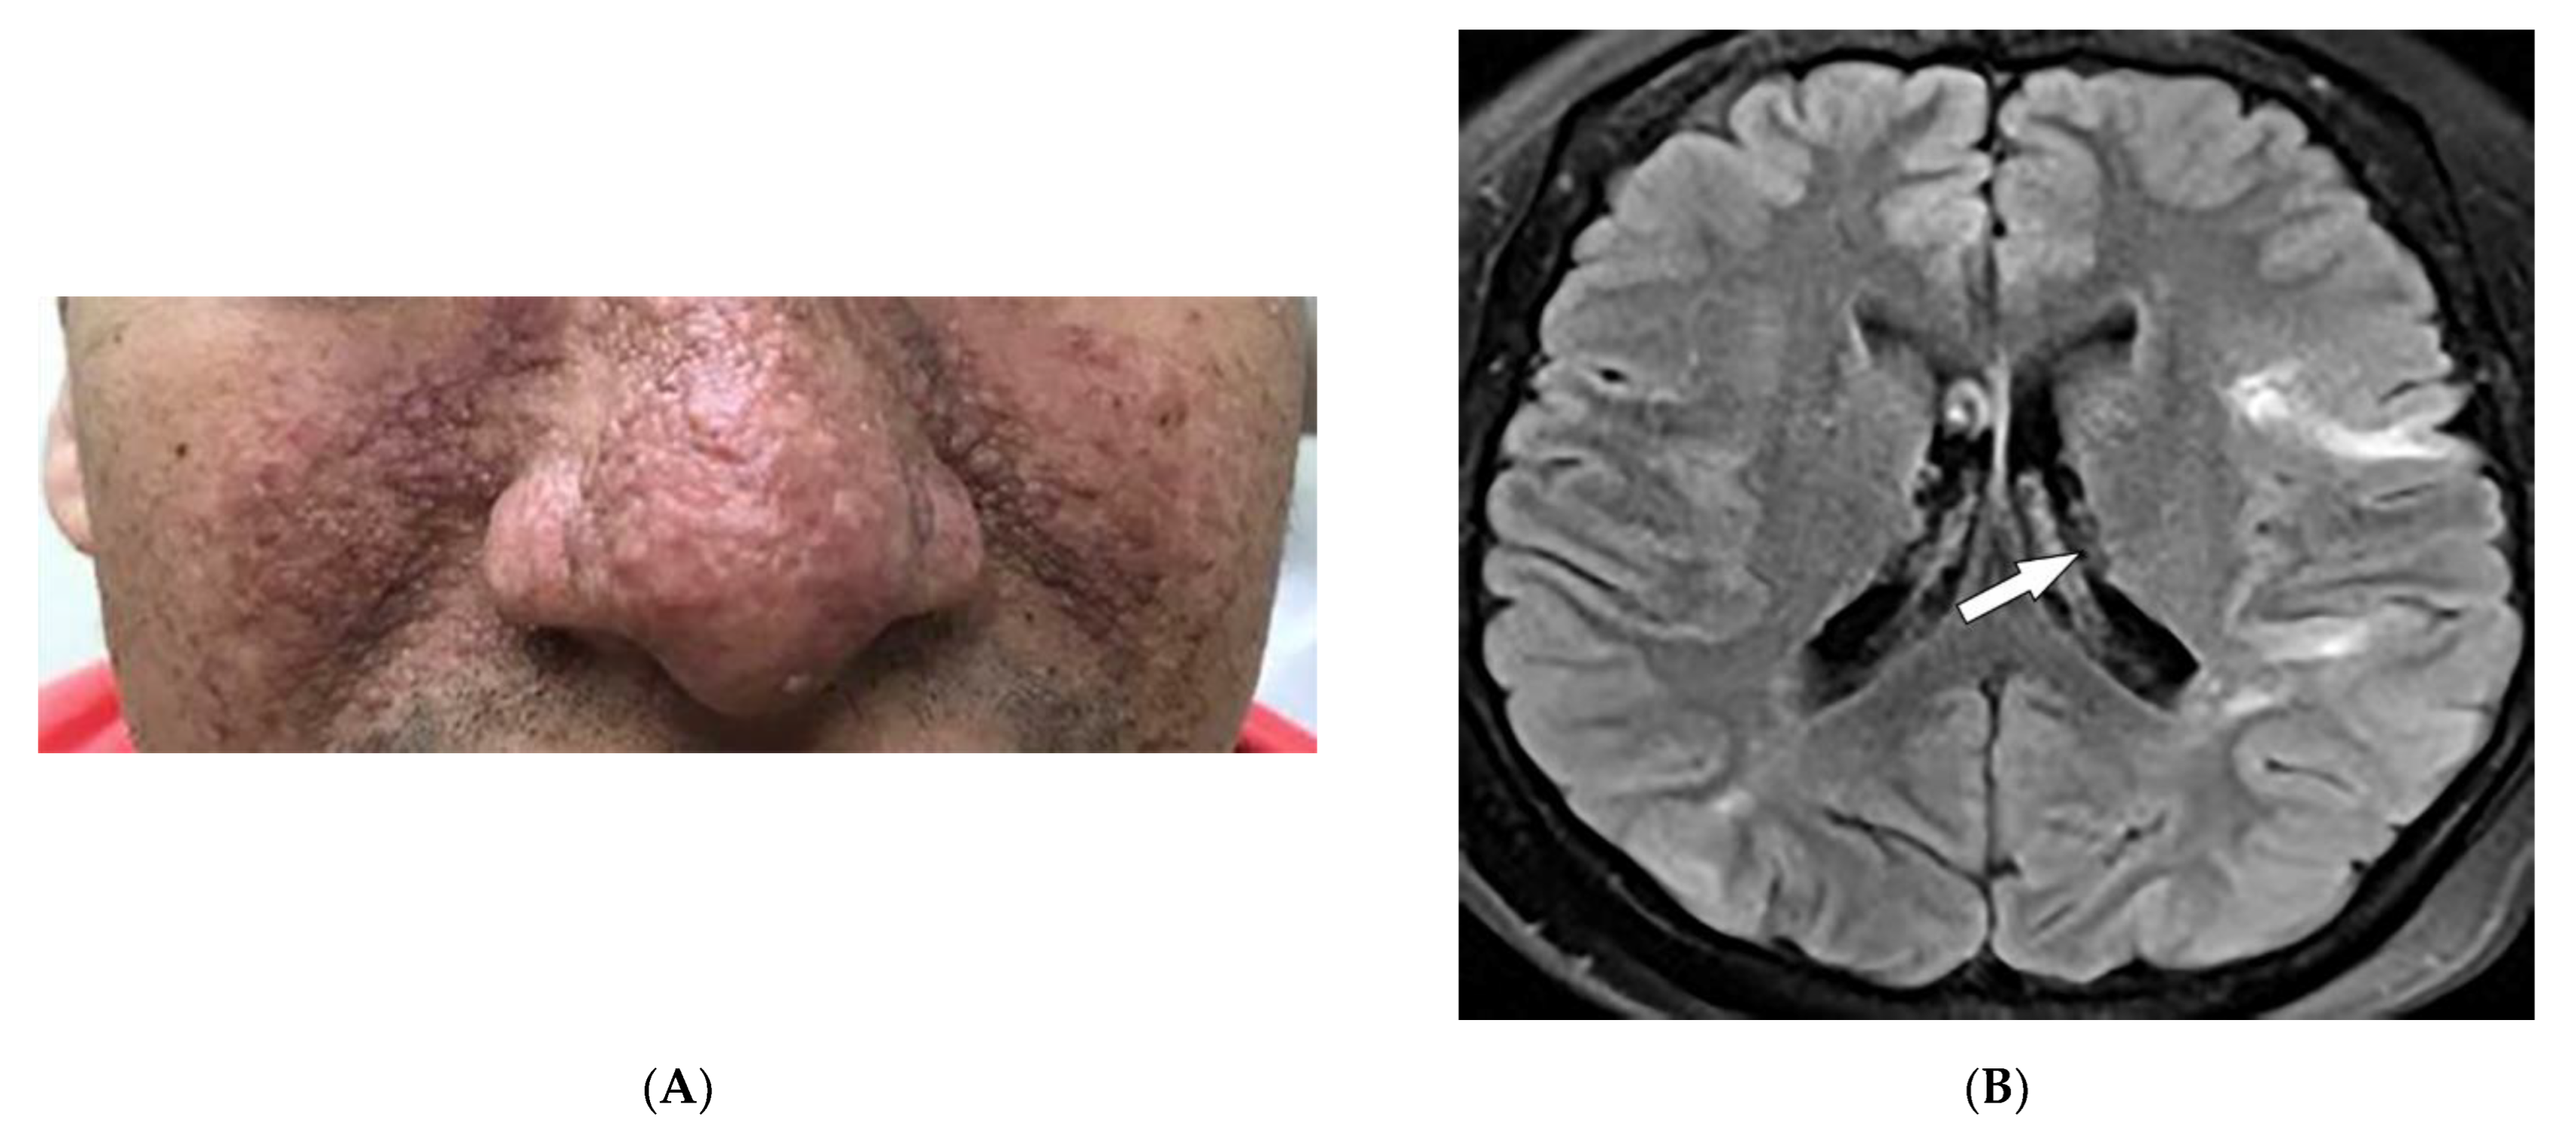

2.2. Sarcoidosis

| Sarcoidosis | Lupus pernio Erythema nodosum Lung nodules and adenopathy neurosarcoidosis Bone lesions | Reticulonodular lung opacities with upper lobe and peri-lymphatic distribution Leptomeningeal enhancement Lacy lytic bone lesions |